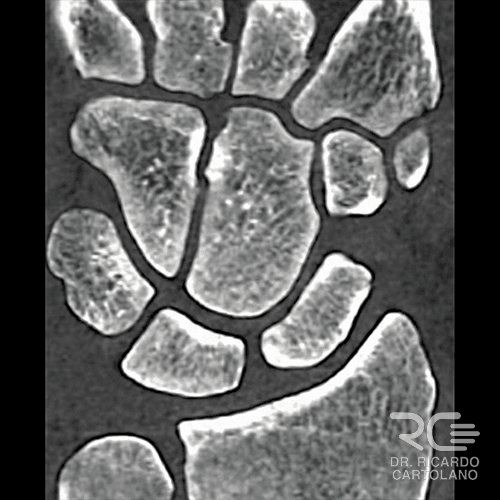

Tomografia Computadorizada

Funciona como um Raio-X avançado em 3D. É essencial no planejamento cirúrgico de fraturas complexas (que envolvem a articulação) e para avaliar se o osso está consolidando (‘colando’) corretamente.